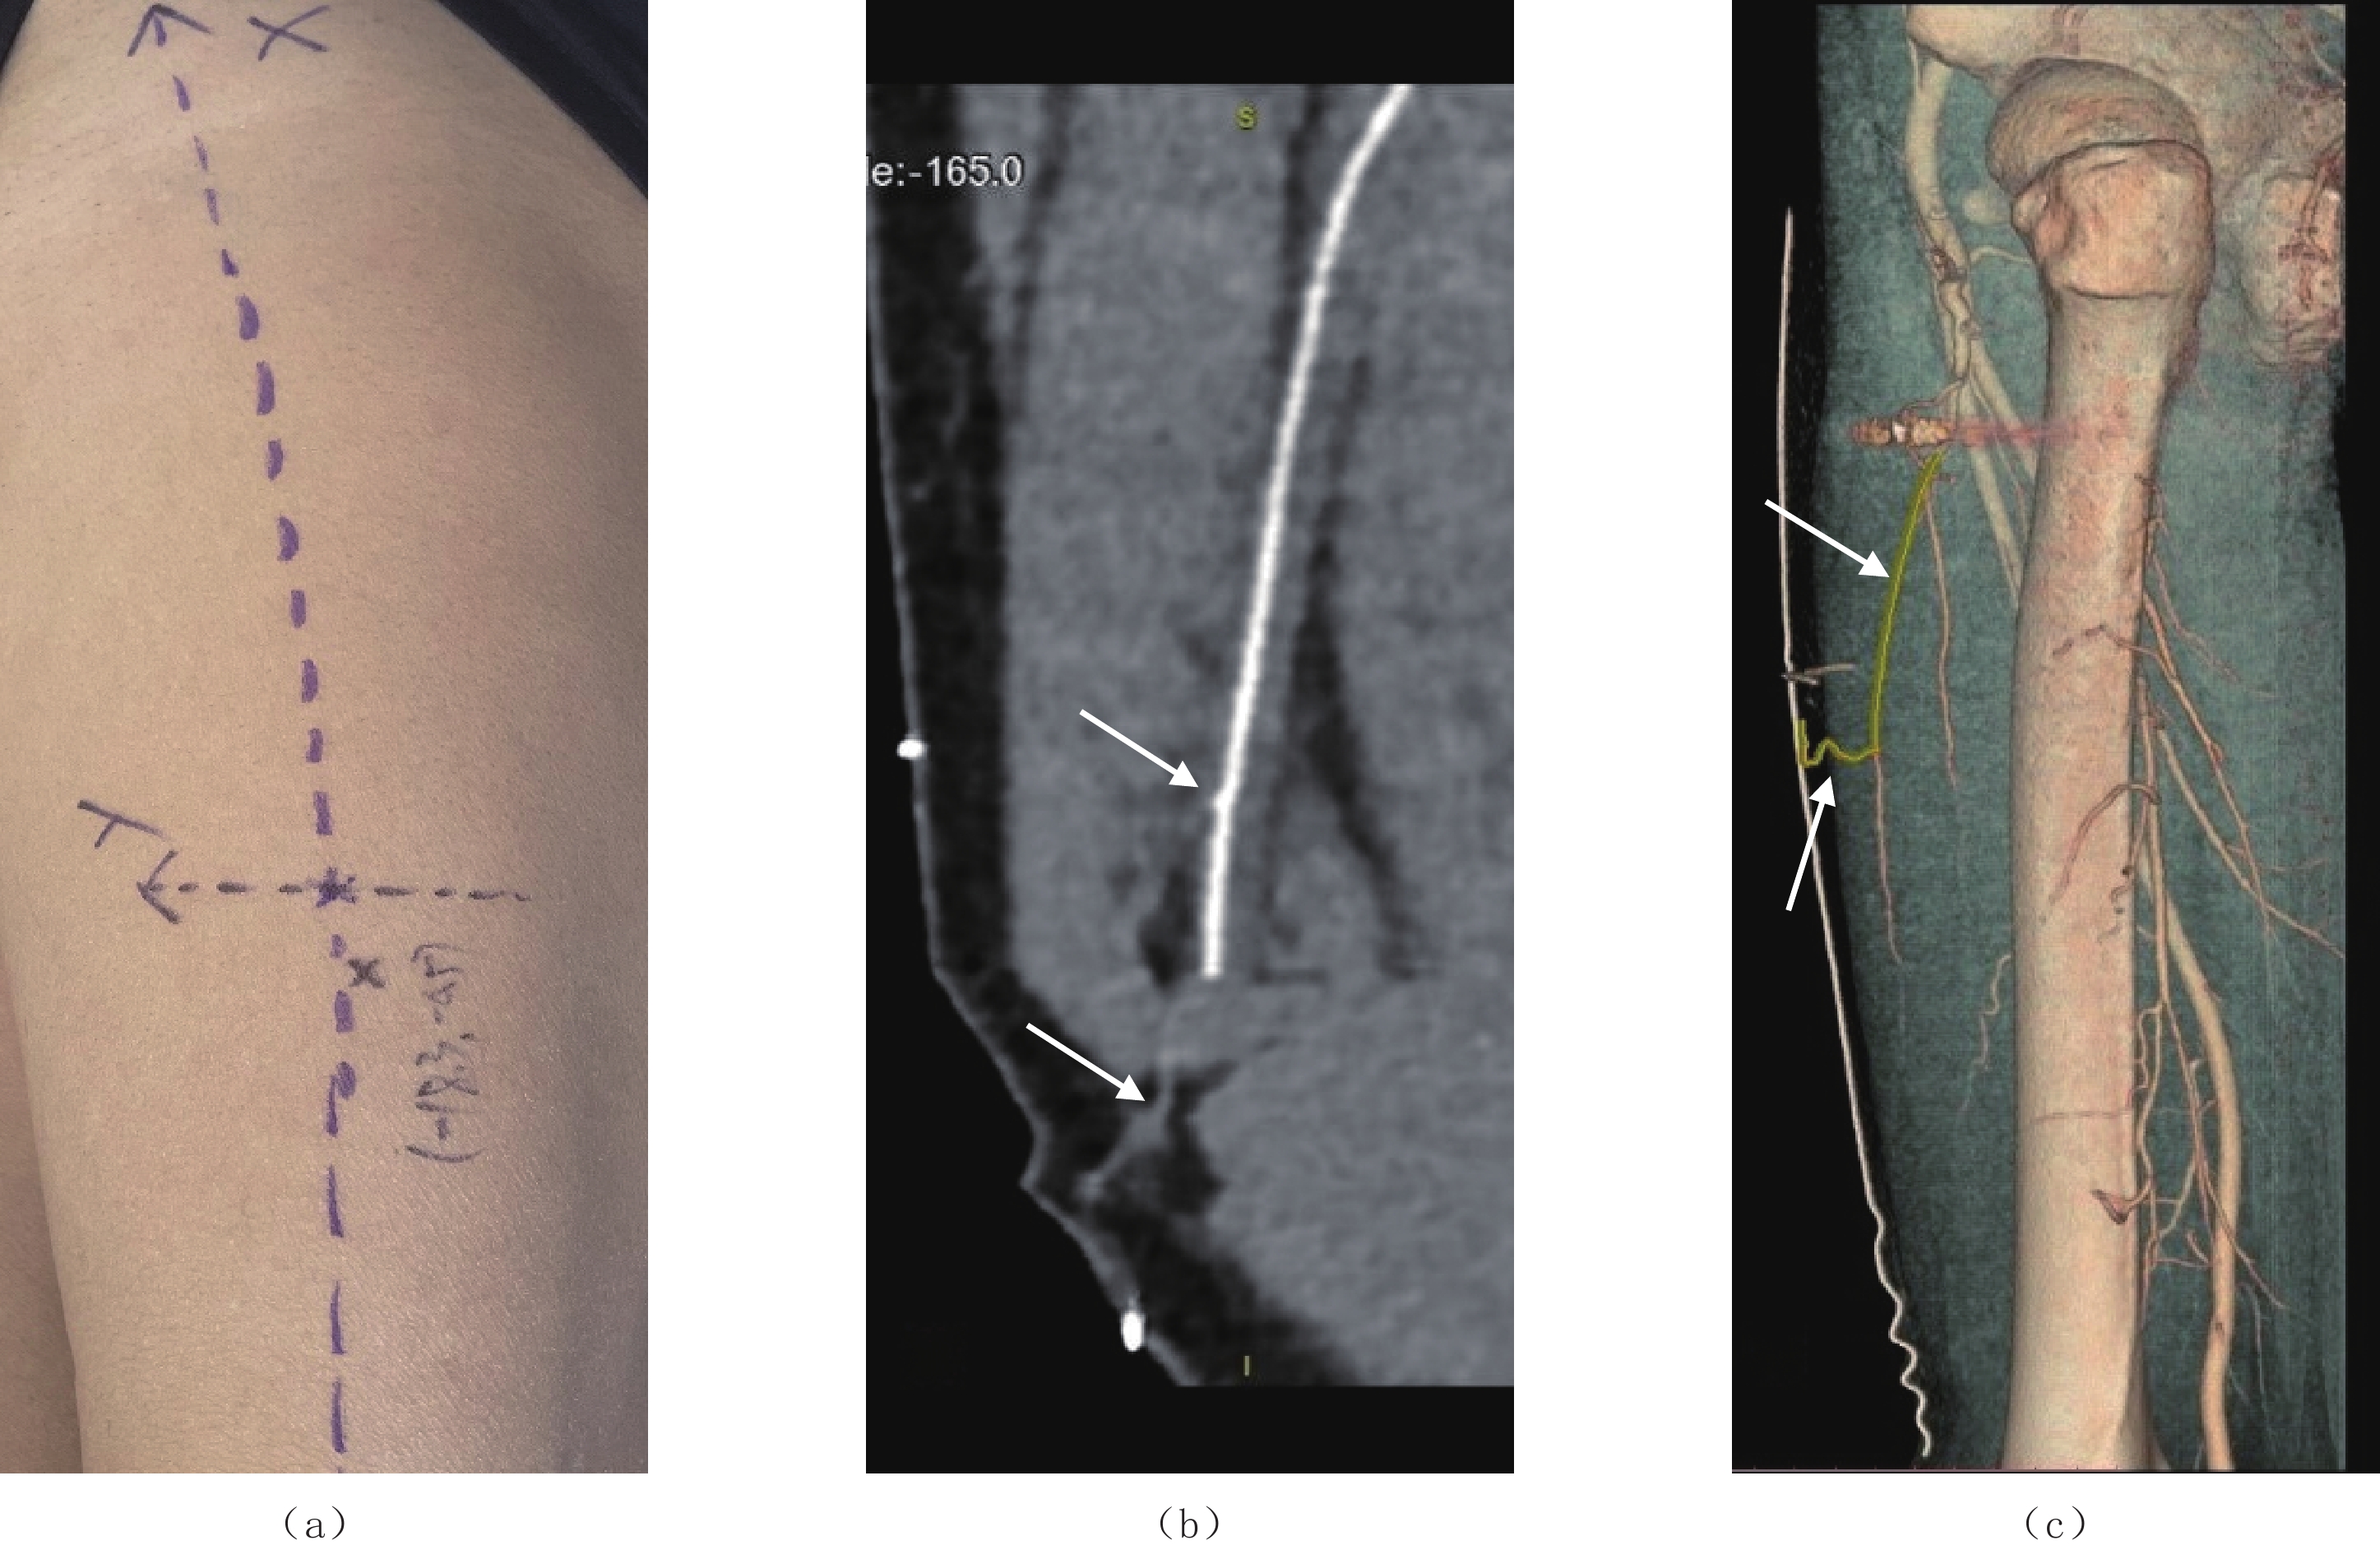

Abstract: Objective: The anterolateral thigh (ALT) flap is a multifunctional diaphyseal flap used to reconstruct head and neck defects. The location, destination, and source of the perforator vessels are crucial for developing a reasonable surgical plan. The small FOV technique can narrow the reconstruction field, increase image resolution, and enhance the spatial resolution of perforator vessels. The two-stage contrast injection method enhances peripheral vessel filling pressure. Multiplanar reformation (MPR) allows coronal reconstruction of the area of interest permitting observation of the distribution of the distal perforator vessels of the lateral circumflex femoral artery. Curved multiplanar reformation (CPR) generates a curved image of the perforator vessels by integrating the curved path of the perforator vessels with the volume-rendering image of the lateral circumflex femoral artery to determine the location and course of the perforator vessels. This study was performed to improve perforator flap vessel visualization using various computed tomography angiography (CTA) scanning and post-processing techniques. Methods: The study group consisted of 13 patients with head and neck tumor defects who underwent improved preoperative CTA scanning between January 2018 and August 2021 at our hospital’s Department of Otorhinolaryngology, Head and Neck Surgery. The control group included 13 patients with no significant lesions in the femoral artery or its branches who underwent non-spectral CT angiography of the bilateral lower extremity arteries between September 2020 and April 2023 at the Radiology Department of Beijing Friendship Hospital, Capital Medical University. Vascular imaging quality was subjectively scored, and the contrast-to-noise ratios (CNR) and signal-to-noise ratios (SNR) of the lateral circumflex femoral artery were objectively evaluated. Results: While SNR in the intervention group was slightly higher than that in the control group, no significant difference was observed between the two groups. The average CNR in the study group was 18.25±7.38, while that in the control group was 7.26±2.64. The CNR in the study group was significantly higher than that in the control group, with a statistically significant difference between the two groups. No significant difference in subjective image quality scores was observed between the study and control groups. All perforator vessels detected on preoperative CTA in the study group were confirmed intraoperatively. Conclusions: Comprehensive application of multiple techniques increased the contrast between the perforator vessels and surrounding tissues, resulting in satisfactory CT image quality. These methods improve the accuracy of image analysis and provide better technical support for clinicians in analyzing the location, course, and source of blood vessels.